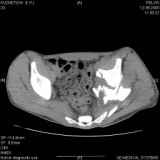

Уважаемые коллеги! Хотелось бы услышать совет по тактике лечения представлленого больного.Поступил после лечения в одном изотделений области. Травма 2,5 месяца назад. После выведенияиз шока был произведен остеосинтез перелома бедра, предплечья, до перевода к нам проводилосьвытяжение по оси шейки бедра за стержень, введенный в большой вертел. На сегодня деформацияригидна, клинически мобильности не определяется. Заранее признателен. P.S. Данный вид травм не включен в перечень "высокотехнологичных операций", направить длялечения по квотам Минздрава очень сложно.

Тяжелый случай... Поздняя реконструкция такого перелома технически сложное дело, вероятность осложнений,неуд.результатов выше(на PubMed article Johnson, Mast, Matta, Letournell results of acetabular reconstruction 20-120 days after injury).

Это обзорные и косые снимки

Привет, Леонид. Оскольчатый высокий двухколонный перелом в такие сроки трогать не надо, т.к. это про такие переломы сказано: "кто с ножом на Ж. пойдет тот в ней и останется...".